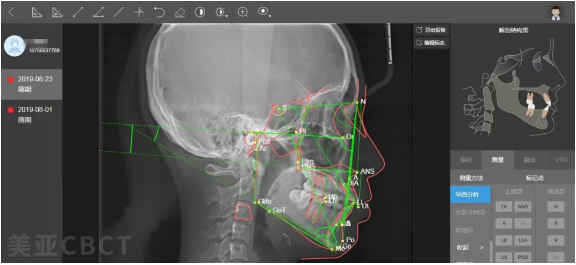

(图片来源网络,侵删)- 强调特定的分析顺序: 先骨骼后牙齿,先硬组织后软组织,先整体后局部。